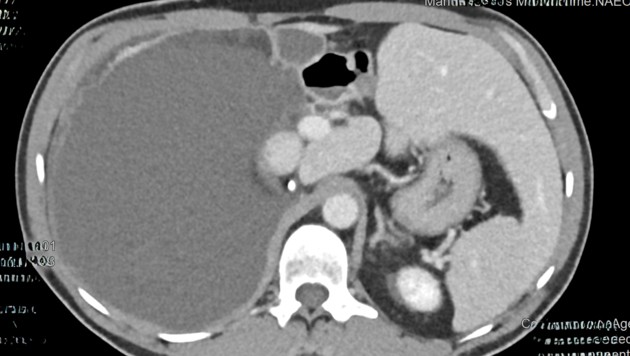

Ein heikler Eingriff ist den Chirurgen der Klinik Oberwart jetzt erfolgreich geglückt. Sie entfernten in einer zweistündigen OP einem Patienten einen 30 Zentimeter großen Tumor.

Denn bei der umfassenden Untersuchung wurde die Ursache für die Symptome schnell klar: Im Oberbauch des Mannes hatte sich langsam ein zystischer Tumor gebildet, der letztendlich auf eine Größe von unglaublichen 30 Zentimetern angewachsen war. „Ein Tumor von solcher Dimension ist selten. Aufgrund der enormen Größe und der Lage des Tumors – zwischen Leber, rechter Niere, großer Körperschlagader und Dickdarm – war die Operation eine Herausforderung“, sagt Primarius Univ.-Prof. Dr. Peter Kornprat, Abteilungsleiter der Chirurgie in Oberwart.